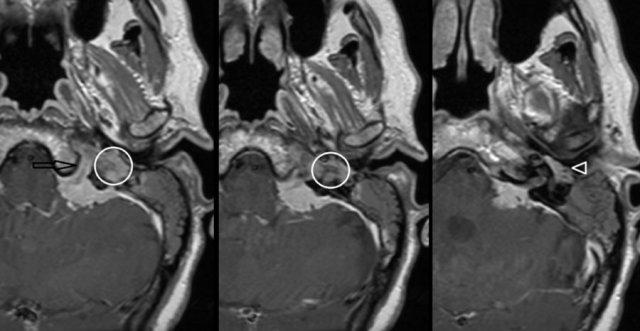

U cận hạch (Paraganglioma)

Cả CT và MRI đều có thể được sử dụng để phát hiện và đánh giá u cận hạch.

Phần lớn u cận hạch màng nhĩ nằm ở ụ nhô (promontory) dưới dạng một khối mô mềm màng nhĩ nhỏ, bờ rõ.

Thông thường, không có hoặc có rất ít tiêu xương xung quanh.

Các khối u nhỏ này được đánh giá tốt nhất bằng CT lát mỏng với thuật toán xương.

CT trục bên trái cho thấy khối mô mềm ở tai giữa (mũi tên).

Không thấy tiêu xương rõ ràng.

MRI chuỗi xung T1W có tiêm thuốc tương phản từ kết hợp xóa mỡ trục bên phải cho thấy tổn thương ngấm thuốc mạnh (đầu mũi tên).